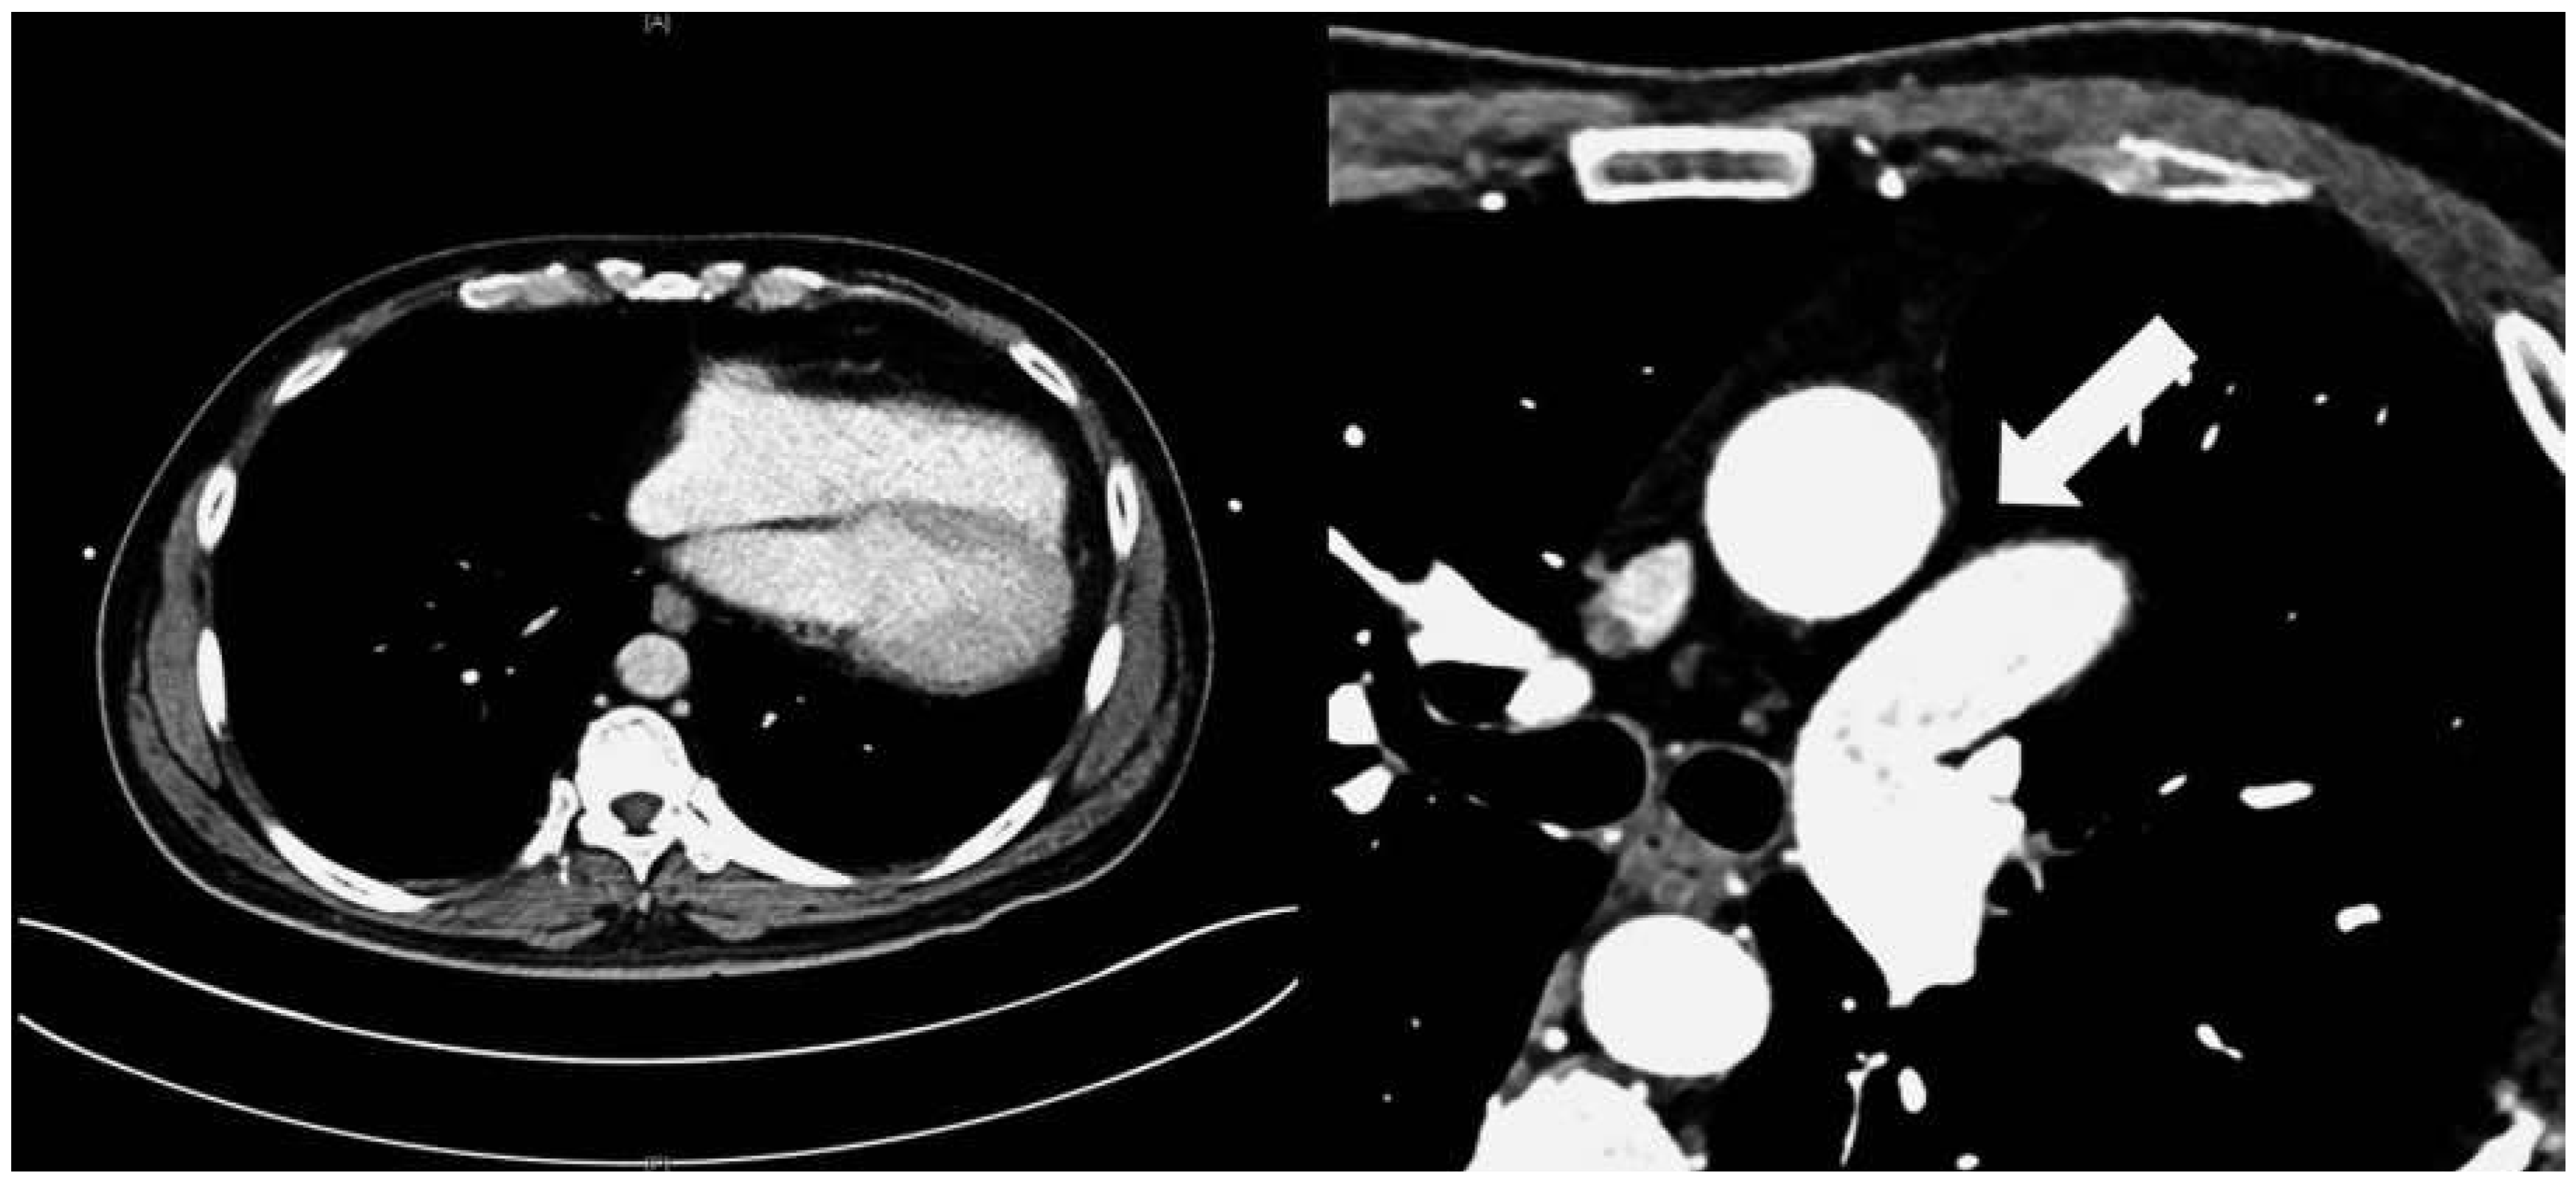

A 57-year-old male presented to the medical outpatient department with typical angina pectoris Canadian Cardiovascular Society (CCS) class II and dyspnoea on exertion during the previous weeks. Additionally he had retrosternal pain at rest and dyspnoea during the previous night. The patient had a a history of untreated arterial hypertension. On initial workup, the patient was in a stable cardiovascular condition with an office blood pressure of 150/88 mm Hg, and the cardiac examination was unremarkable. Blood tests revealed serially negative high-sensitivity troponins. Glycated haemoglobin was 6.4%, consistent with prediabetes, and lowdensity lipoprotein cholesterol was 2.5 mmol/l. An electrocardiogram (ECG) showed sinus rhythm, right axis deviation, signs of an incomplete right bundle-branch block with rR’ morphology in leads V1 to V4, and lateral displacement of the transition zone in the precordial leads, but no signs of acute ischaemia (Figure 1). On echocardiography, the image acquisition was difficult with a typical long axis view acquired in the fifth intercostal space in the midaxillary line (Figure 2) and apical views acquired from a posterolateral window (Figure 3). Computed tomography angiography (CTA) of the heart showed that the entire heart was displaced leftwards into the left hemithorax. Also evident was a lingula of lung tissue interposed between the aorta and the pulmonary artery indicating a congenitally absent pericardium (Figure 4). Additionally, the CT scan revealed coronary artery disease with soft plaques and >70% stenoses of the left anterior descending artery (LAD), the left circumflex artery (50%–70% stenosis) and the first marginal branch (>70% stenosis). Considering the diagnosis of a congenitally absent pericardium, the ECG was repeated, with leads V7–V9, showing a normal R-progression from V4 to V9 (Figure 5). Coronary angiography with primary stenting of a 95%–99% stenosis of the LAD artery and a 75%–95% stenosis of the first marginal branch resulted in complete resolution of symptoms.

Figure 4. Computed tomography scan showing the lateral displacement of the heart. The arrow indicats lung tissue between the aorta and the main pulmonal artery – pathognomonic sign for congenital left sided absent pericardium.

Congenitally absent pericardium is a rare condition found in 1/10 000 autopsies with morphological patterns of: total bilateral absence (extremely rare); partial left absence (70%); and partial right absence (17%) [1]. It may be associated with other congenital defects such as atrial septal defects, persistant ductus arteriosus, bicuspid aortic valve or tetralogy of Fallot [2]. Most patients are asymptomatic but absent pericardium may cause paroxysmal, stabbing, nonexertional chest pain. In partial left absence severe complications may be caused by herniation of parts of the heart resulting in shortness of breath, syncope or sudden death [1,2]. On ECG, partial right bundle-branch block is common and displacement of the transition zone in the precordial leads is seen as a result of the displacement of the heart [2]. On transthoracic echocardiography, the standard views are found to be displaced leftwards as is exemplified in Figure 2. The diagnosis is usually established by use of CT or magnetic resonance tomography showing displacement of the heart into the left hemithorax and lung tissue interposed between the aorta and the main pulmonary artery [2]. In symptomatic patients, and especially in patients with risk factors or symptoms of herniation, surgical therapy with pericardioplasty may be performed [1,2]. Our patient was symptom-free after coronary angiography and no treatment due to the congenitally absent pericardium was necessary.